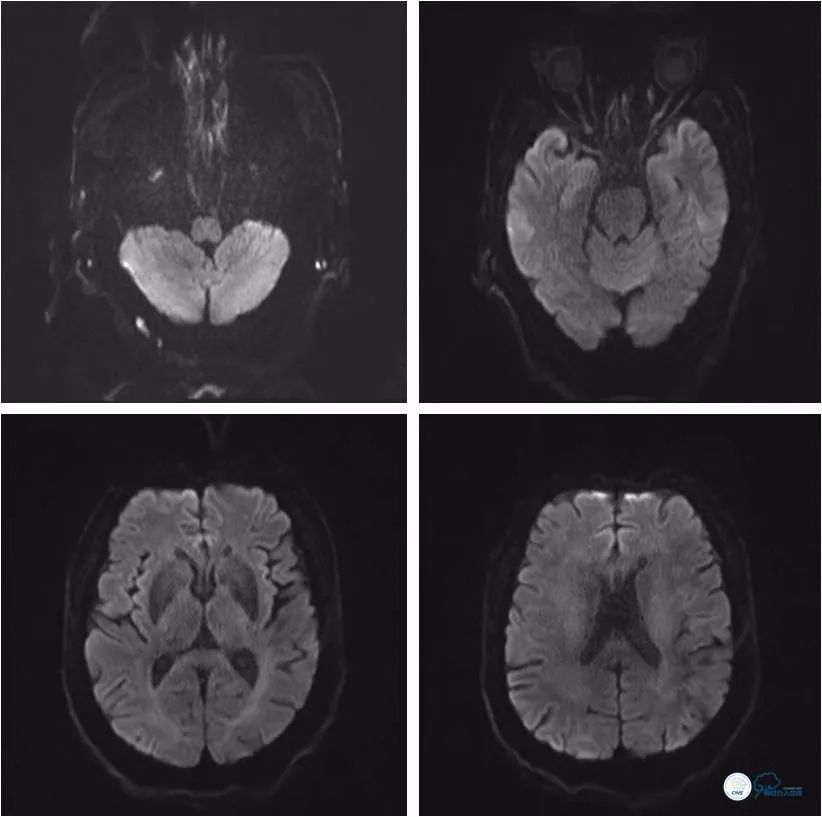

头颅MRI:双侧小脑半球、右侧丘脑多发急性梗死灶。

入院后头颅MR(2018-6-30):DWI未见明显新鲜梗死病灶(图1)。

图1